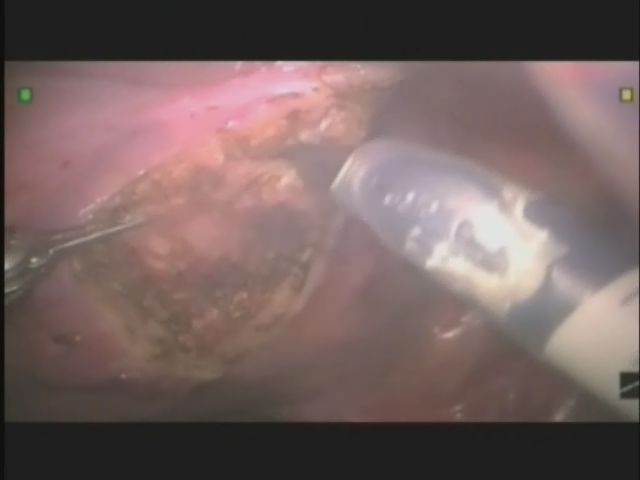

In Utero Robotic-Assisted La..

In Utero Robotic-Assisted La..

Drew Freilich, MD; Carlo C. Passerotti, MD, PhD; Hiep T. Nguyen, MD / CINE-MED